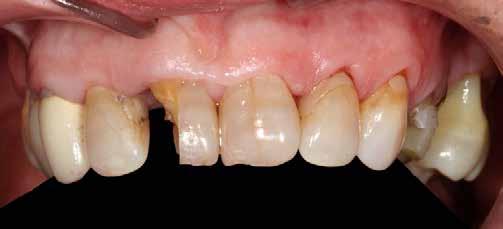

Az 50 éves nőpáciens az alsó és felső állcsont területén egyaránt panaszt (fájdalom, ráharapási érzékenység) okozó, harmadfokban mozgatható fogak miatt jelentkezett rendelőnkben. Az általános anamnézisben említést érdemlő betegség, műtét nem szerepelt. Az elvégzett klinikai és radiológiai vizsgálatok (1–2. ábra) alapján fogai reménytelen parodontális státusúnak bizonyultak, hosszú távon sem megtartásuk, sem protetikai célú felhasználásuk nem volt lehetséges. A parodontális prognózis a fogak eltávolításának abszolút indikációját jelentette. Ezáltal mindkét állcsontban teljes foghiány kialakulásával kellett számolnunk. A protetikai szemléletű, „visszafelé” tervezés elveit követtük a hosszú távú funkcionális, esztétikai siker és szöveti stabilitás elérése érdekében: mindkét állcsontban overdenture típusú fogpótlás készítése mellett döntöttünk. A megfelelő implant-protetikai rehabilitáció alapja az implantátumok megfelelő pozicionálása. A korábbi parodontális kórfolyamat következtében a processus alveolarisokat érintő eredendő csontdeficittel kellett számolnunk, amelyet tovább súlyosbíthatott volna a hagyományos extrakciós technikát követő involúciós atrófia. Ezért a páciens kivizsgálása és megfelelő előkészítése után a fog eltávolításával egy időben PRF

A fogak eltávolításának indikációja

A bukkális csontállomány teljes felszívódását és a fogak jelentős mobilitását okozó előrehaladott parodontális folyamat, a fogak eltávolításának abszolút indikációját jelenti. Tapasztalataink szerint ilyen esetben a fogak megtartását célzó regeneratív kezelésektől hosszú távú siker nem várható, az adekvát oki terápia a fog eltávolítása.